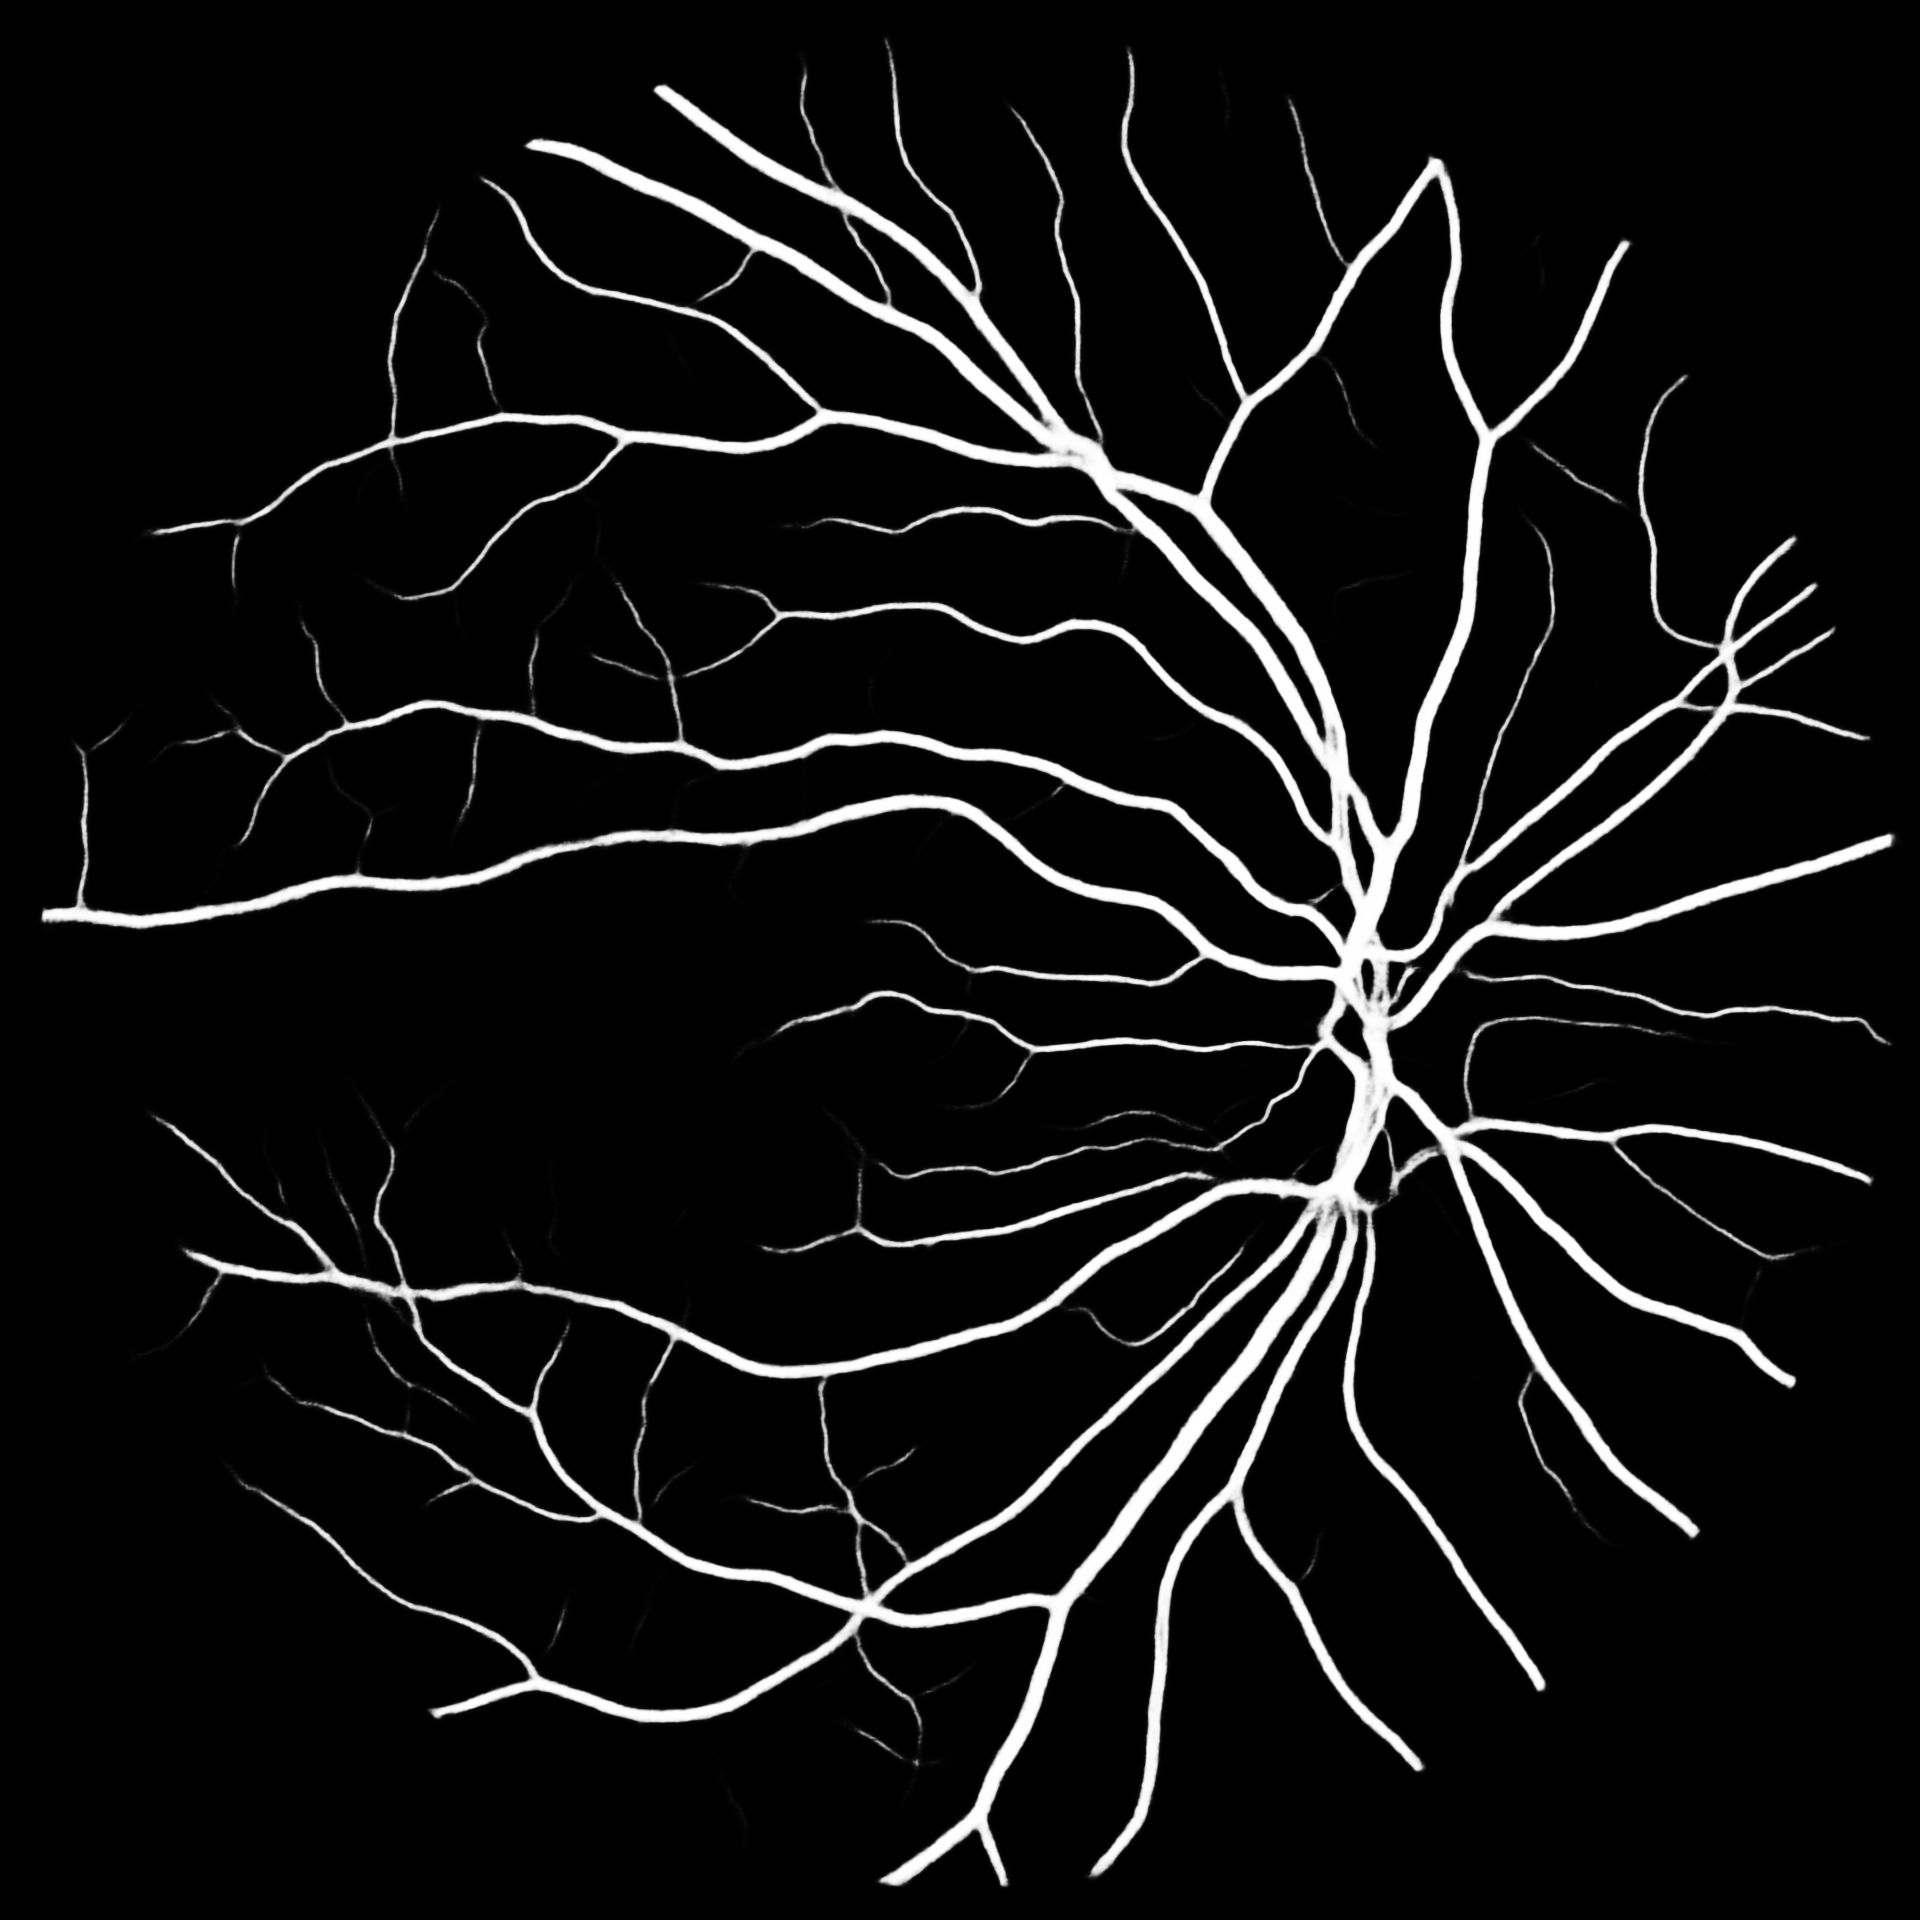

VI Evaluation

To put our results into perspective, Table V compares previous works to our methods. We report the -score for our results together with their standard deviation. Overall M2U-Net and DRIU trained on COVD are competitive, with the best performance on the high-resolution dataset HRF, where a new state-of-the-art F1-score could be reached. Additional metrics such as accuracy, sensitivity, precision and specificity are available in the documentation of our software package. Further, to the available public datasets, we trained M2U-Net on COVD for a private target dataset with a resolution of 1920x1920 for which no ground-truth data is available. The predicted vessel probability maps are displayed in Figure 5. While we can only make subjective statements, we find that the generated probability maps are of good quality, with the majority of main vessels being detected, even in presence of pathologies. An illustration of predicted vessel maps versus ground truths for M2U-Net on HRF is provided in Figure 4.

HRF

COVD

COVD– SSL